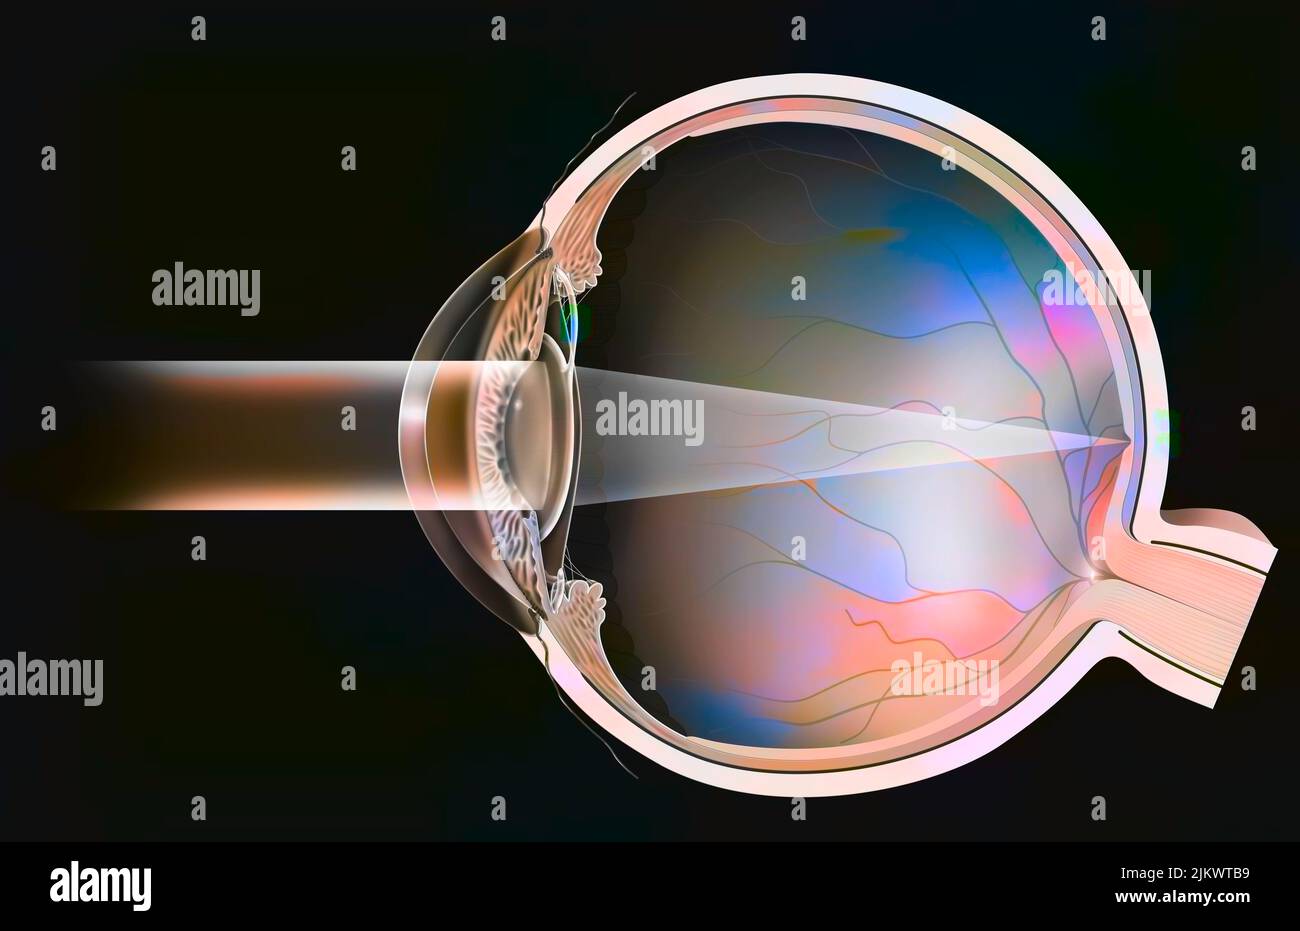

RF2JKWT9A–Oeil, cataracte, phacoémulsification - étape 2: Consiste à casser la lentille avec une sonde.